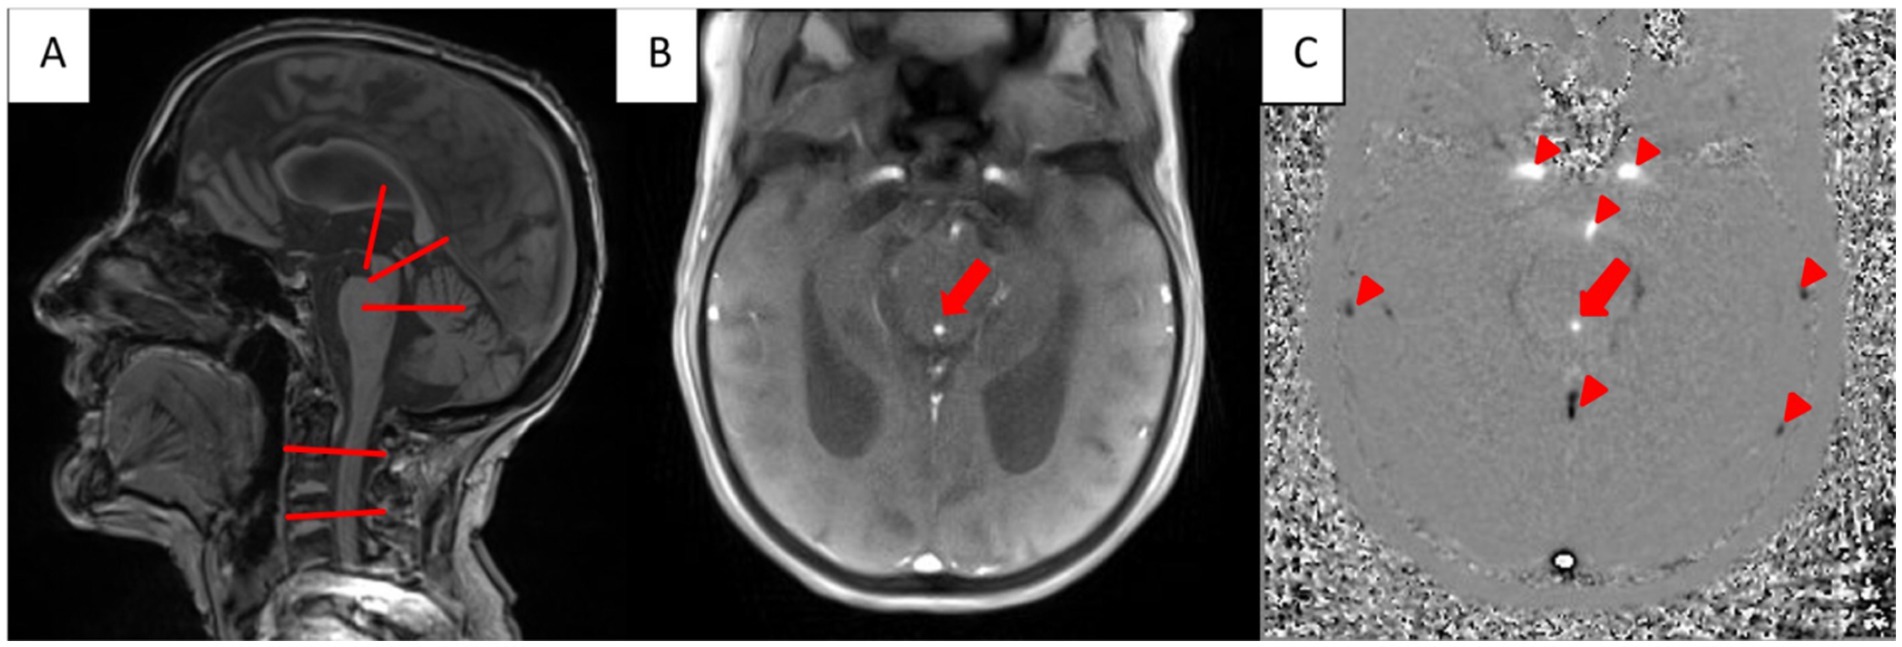

Figure 2

(A) T1-weighted MRI in sagittal plane. The red lines mark the ROIs for the CSF-flow measurements: third ventricle, aquaeductus mesencephalic, fourth ventricle, extracranial: subarachnoid space (second and fourth cervical vertebra). (B) Anatomical magnitude real time phase contrast MRI in a transversal plane showing CSF-flow in the aquaeductus mesencephalic (red arrow). (C) Corresponding phase contrast image with cranially directed CSF-flow (blue arrow). Note that in the phase contrast image cranially directed flow is visualized hyperintense and caudally directed flow hypointense (Arrowheads mark the carotid arteries and the basilar artery (hyperintense) and draining veins/sinus).

CSF-flow was measured using magnitude images of the anatomical structures for reference and phase-contrast images that provided velocity and flow direction information. Representative magnitude and phase-contrast image series used for CSF-flow measurements are shown in Figures 2B,C as well as are available in the Supplementary Videos 1, 2.